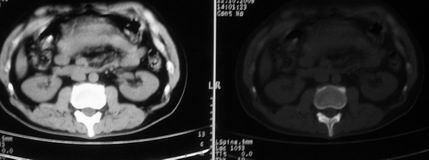

以下是引用余辉在2008-10-23 16:14:00的发言:[br]腰椎体棱角分明,小关节退变部分隔合,骶髂关节部分融合,考强脊炎